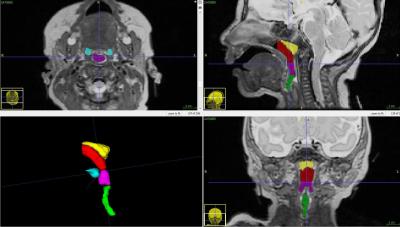

Forty-nine of the infants were born preterm; at the time of the MRI, their corrected mean gestational age was 38.4 weeks. Forty-seven of the newborns were born full term; they received MRIs at 1.7 weeks of age. The airway structures of interest included the nasopharynx (the upper part of the pharynx), oropharynx (located at the back of the mouth behind the oral cavity), hypopharynx (the entrance into the esophagus), adenoids and tonsils. The team displayed the volumetric imaging in three perpendicular planes and a three-dimensional model.

"Nasopharyngeal volume of full-term infants was 495.6 mm, compared with 221.1 mm in preterm infants. Oropharyngeal volume of full-term infants was 313.6 mm, compared with 179.3 mm in preterm infants," Smitthimedhin says.